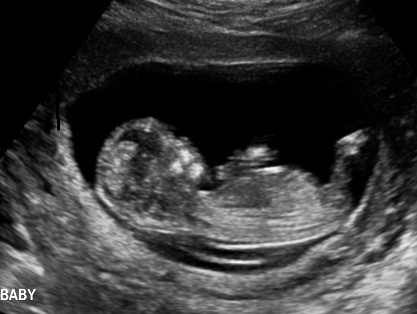

Well went for my scan today, baby was very photogenic! I was exactly 13 weeks.

Not sure what i feel, i am so in love with this baby already. Its funny coz even tho I swayed i am realy not bothered about gender, will not be finding out gender until birth but still would love guesses. Tech gave me her feeling what she thought.

Attachment 3732Attachment 3733Attachment 3734